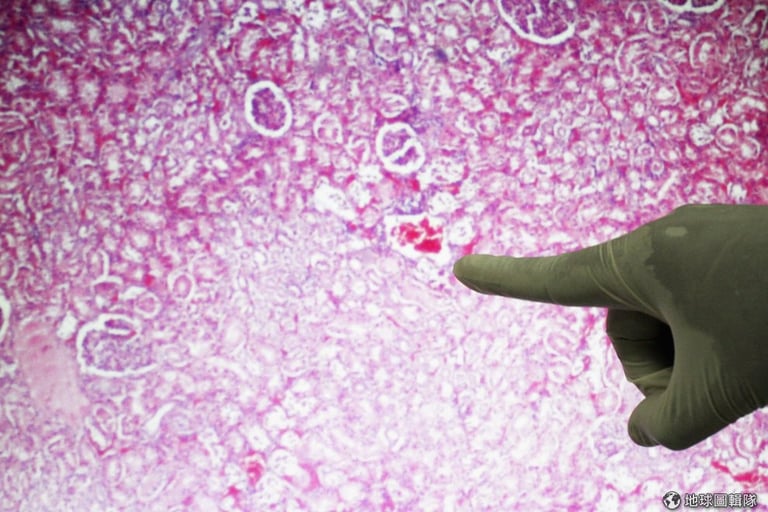

文章插圖

China Photos/Getty Images

gettyimages